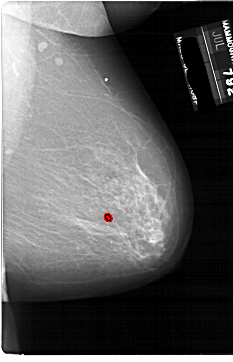

A_1861_1.RIGHT_MLO

RIGHT_MLO LINES 6871 PIXELS_PER_LINE 4426 BITS_PER_PIXEL 12 RESOLUTION 43.5 OVERLAY

FILE: A_1861_1.RIGHT_MLO.OVERLAY

TOTAL_ABNORMALITIES 1

ABNORMALITY 1

LESION_TYPE CALCIFICATION TYPE PLEOMORPHIC DISTRIBUTION CLUSTERED

ASSESSMENT 4

SUBTLETY 2

PATHOLOGY BENIGN

TOTAL_OUTLINES 1

BOUNDARY